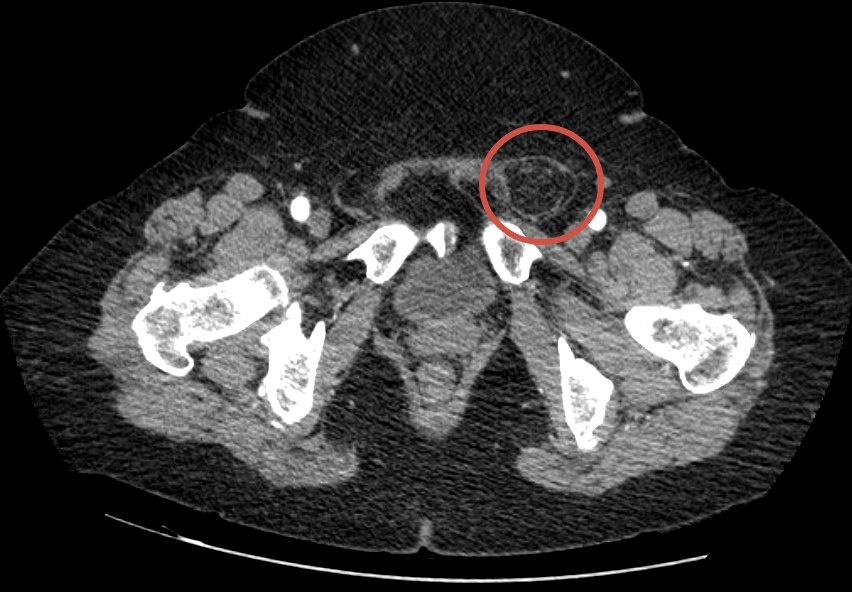

Компьютерная томография показала паховую грыжу с начальными признаками ущемления большого сальника.